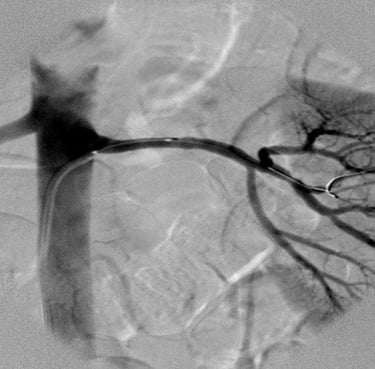

65 years old man from Azamgarh came to me with severe chest pain post CABG which was done in 2021.....

Patient was immediately taken for coronary Angiography which shows LIMA was 100% blocked which was stented Patient was completely pain free since then and living a good quality of life Today he came to meet me in my OPD in tamkuhi raj with smiling face....